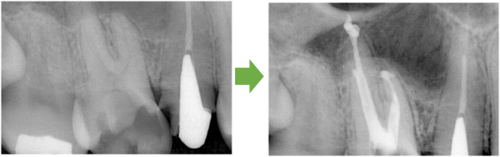

抜髄 右上の小臼歯 川口の歯科 歯医者 さかえ歯科クリニック

2014年12月17日

川口の歯科 歯医者 さかえ歯科クリニック